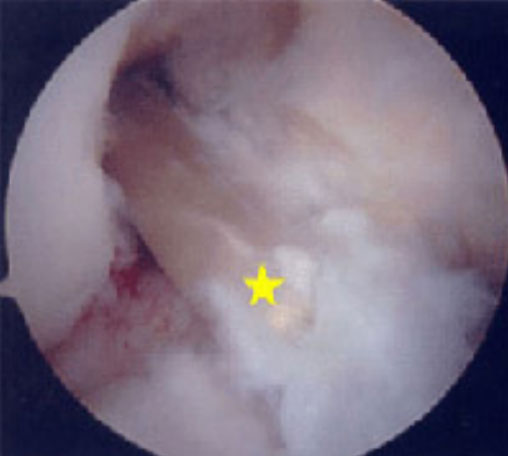

Hình ảnh nội soi khớp cho thấy rách sụn chêm trong ở khớp gối có tổn thương DCCT mãn tính. Trong trường hợp này, phần rách của sụn chêm bị đẩy về phía trước [vị trí sao vàng] và gây kẹt khớp [gọi là rách sụn chêm dạng“quai xô”], làm cho bệnh nhân không thể duỗi thẳng chân.

Hình ảnh nội soi khớp cho thấy tổn thương sụn khớp trong khớp gối có tổn thương DCCT mãn tính.